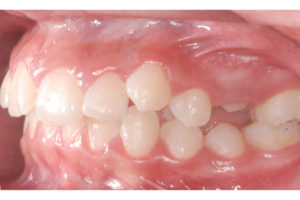

Documento utilizado en todo procedimiento odontológico y en cualquier especialidad, consiste en una secuencia de fotos faciales y dentales en diferentes ángulos, que permiten un diagnostico ideal y evaluar los avances del tratamiento al tener fotos posteriores, además es un documento legal.